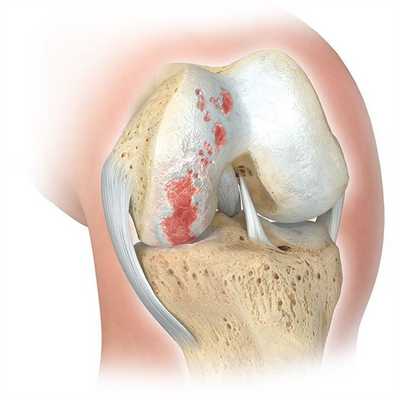

Деформирующий остеоартроз — одно из ведущих заболеваний опорно-двигательного аппарата. Он проявляется дегенеративно-дистрофическими изменениями суставных поверхностей. Частота встречаемости составляет от 3 до 12% среди взрослого населения. В этом показателе на первом месте стоит поражение тазобедренного сустава, а на втором - коленного.

Если сустав поражен указанным на изображении образом, то возможна его частичная замена.

Основной метод лечения - постановка эндопротеза вместо поврежденного сустава. Раньше выполнялось преимущественно тотальное эндопротезирование коленного сустава, однако сейчас активно развивается другое направление - одномыщелковое (частичное) эндопротезирование.